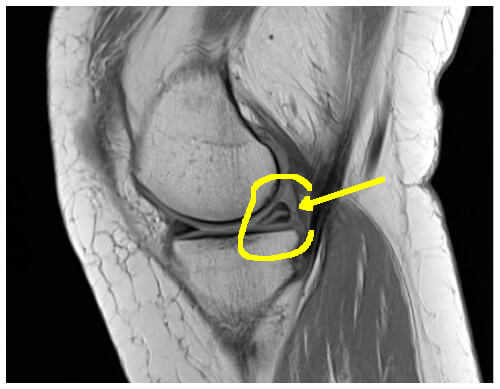

IRM

C'est une lésion mixte dégénérative et mécanique

Parfois, la fissure dégénérative (2) traverse le ménisque. Le liquide articulaire peut alors s'échapper par la fissure et s'accumuler à l'extérieur du ménisque, formant un "kyste" (1). Ce kyste méniscal douloureux par son volume, est en général au niveau du ménisque externe et le plus souvent chez le coureur.